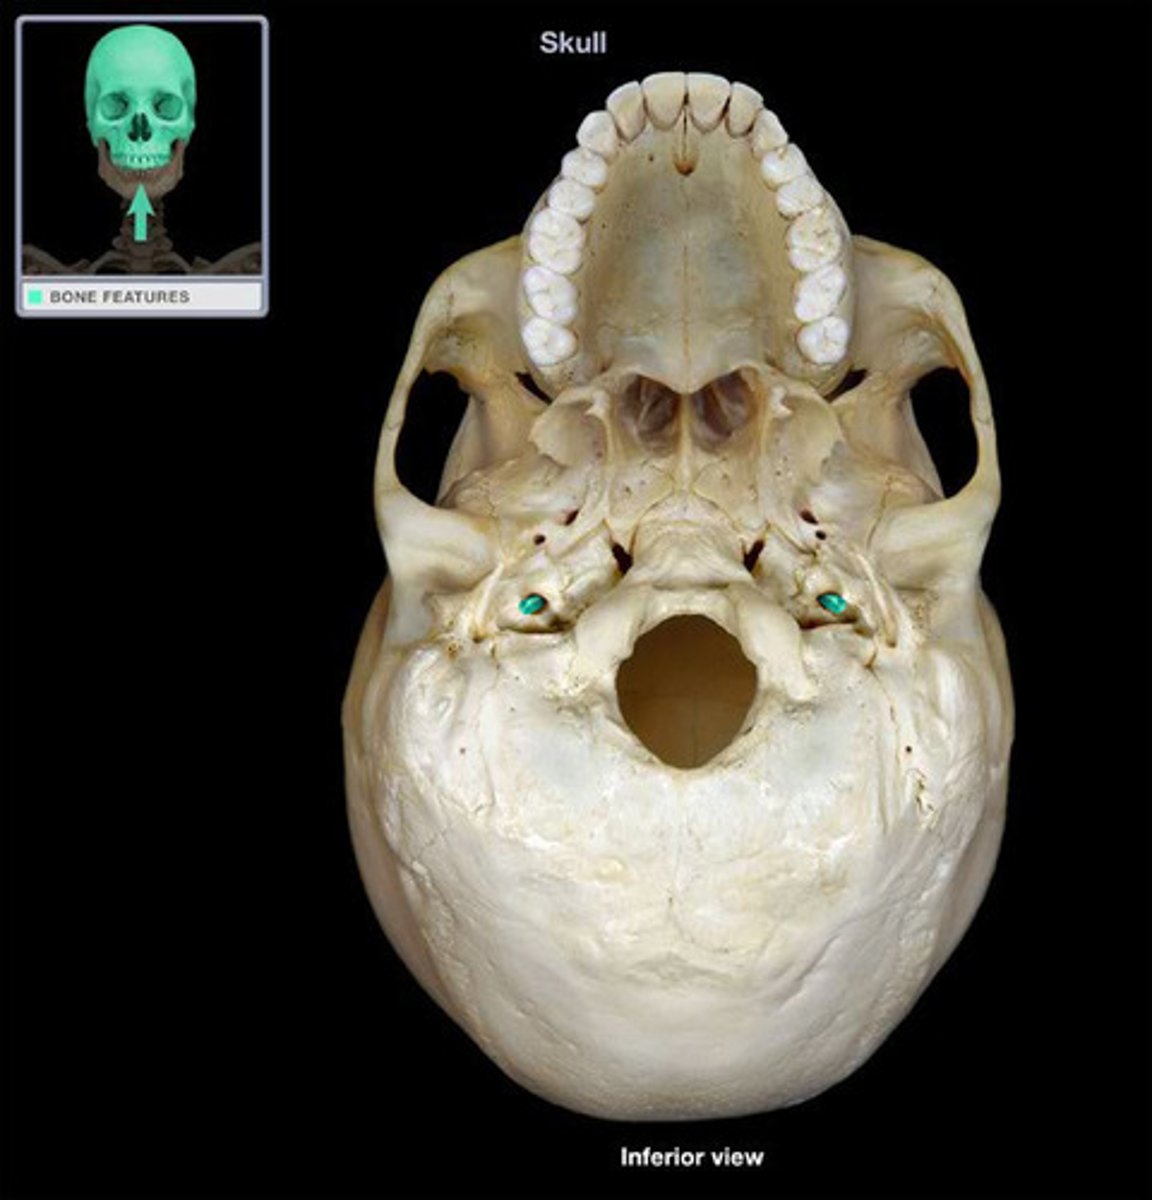

Occipital Bone

Condyles

Foramen Magnum

Jugular Foramen

Jugular Foramen

Carotid Canal

Sphenoid

Palantine Bone

External Occipital Protuberance

Superior nuchal line

Incisive foramen

Alveolar processes